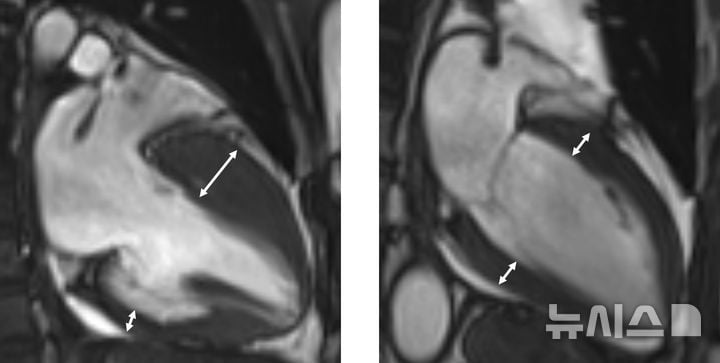

의료 현장에서는 심장초음파, 자기공명영상(MRI) 등 첨단 영상 진단과 유전자 검사로 심근 비후의 정확한 원인과 조직학적 변화를 판별한다. 최근에는 심근 내 섬유화, 지방변성 여부까지 세밀히 확인할 수 있어, 개별 환자 맞춤형 위험 예측 및 치료결정이 가능해졌다. 특히 고위험군 환자의 경우, 실신 경험, 돌연사 가족력, 심실빈맥, 혈압 저하 소견을 기반으로 평가 점수를 산출해 이식형 심실제세동기 등 예방적 시술을 조기에 도입하는 사례가 늘고 있다. 기존 약물치료로 증상이 조절되지 않는 경우에는 심근 절제 수술, 관상동맥 알코올 주입 시술 등 중재 치료도 병행된다.